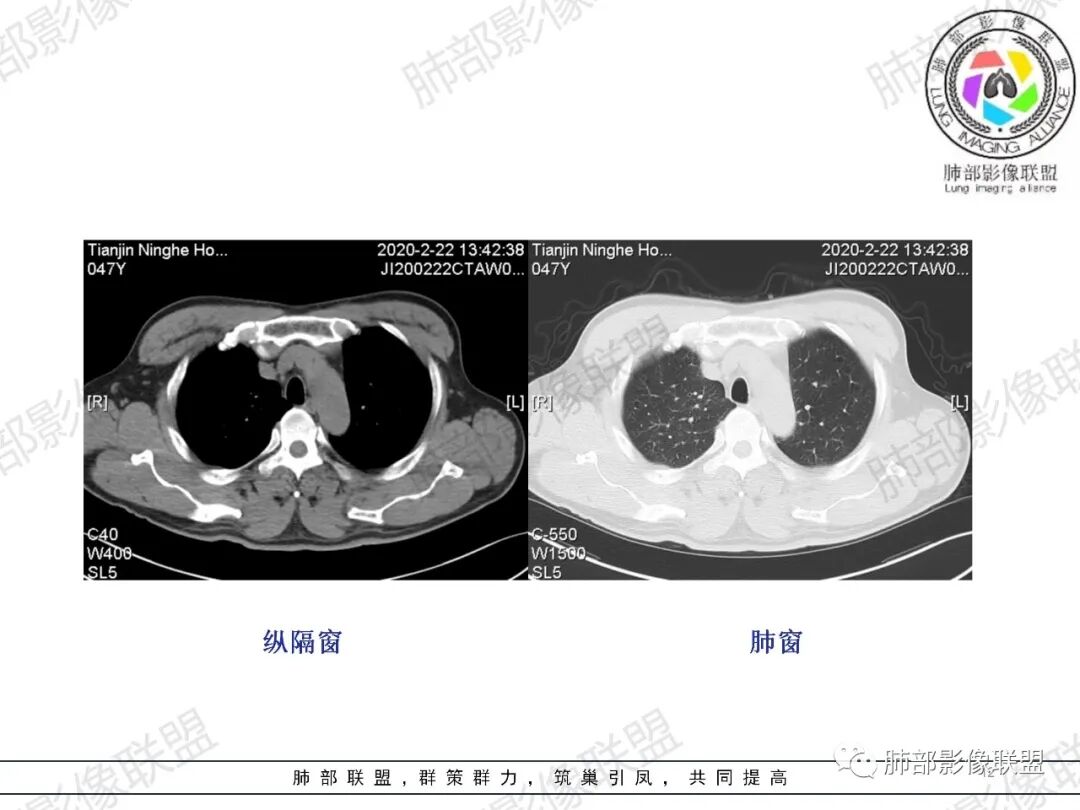

杨泽锋:右肺尖病灶由结节赢、索条影、斑片状影,考虑结核右肺下叶胸膜下楔形斑片状影,因为临床上有胸痛,发热又不明显,首先会想到肺梗,建议增强看看

马春平(张家港市一院胸外科):中年男性、低热、痰血、胸痛 、血象高,右上叶多发结节、疑似空洞、渗出、纤维条索、树芽,右下肺胸膜下与胸膜平行GGO肺泡和小叶间隔增厚,考虑二元论:右上结核、右下肺梗

一切∮随缘:右肺肺尖段多发结节片状高密度影,部分伴有反晕征,边界欠清楚,部分伴有纤维索条,支气管显示欠佳,小叶间隔增厚,周围血管束增粗,(考虑结核可能)右肺下叶胸膜下片状磨玻璃影,与胸膜相贴,与肺组织交界面清楚,实性偏少,考虑:肺栓塞?病毒?OP?

王秀仙:右肺上叶可见结节及斑片影,部分呈反晕征,边缘清晰,右肺下叶后基底段胸膜下磨玻璃样实变影,呈扇形,内部见细网格,右肺上叶考虑结核。右肺下叶考虑肺栓塞,鉴别病毒肺炎。

小兜:男,47岁,胸闷气短入院,一天前无明显诱因胸闷气短伴呼吸困难,夜间出现右侧胸痛,与呼吸及体位有关,曾有一次痰中带血。CT示右肺上叶尖段多发结节,条索影,可见树芽征及反晕征。右肺下叶胸膜下片状密度增高影,宽基底与胸膜相连,成扇形。综合考虑右肺上叶尖段结核可能;右肺下叶肺栓塞?病毒性肺炎?

琦遇:右肺上叶结核基本明确,考虑活动性,有钙化、反晕征、结节、斑片、纤维索条;右肺下胸膜下GGO,内大小网格,胸膜增厚,患者胸痛,咯血,首先考虑PE,下一步增强CTPA以明确

微微笑:右肺上叶斑片、结节、索条影,边缘较清晰,见反晕斑片,考虑结核。右肺下叶宽基底磨玻璃影,网格样改变,胸膜增厚,结合病史,考虑栓塞。

三个石头:右肺上叶结节,斑片,条索,考虑结核。右肺下叶大片磨玻璃,有胸痛,咳血,考虑肺栓塞,建议增强。鉴别病毒肺炎

水晶石头:患者中年男性,胸闷、气促1天。伴右胸痛及痰中带血。否认结核、心脏疾病等病史。查体无特殊。完善血常规白细胞计数、中性粒细胞百分比及C反应蛋白升高。心电图、B超、凝血功能、降钙素原、脑钠肽正常。胸部CT:右肺上叶尖段多发结节、斑片、纤维条索影,见小叶间隔增厚及反晕征。右肺下叶后基底段胸膜下片状磨玻璃影,见小叶内间隔增厚。右侧胸膜增厚,未见明显淋巴结增大。综合考虑右上肺结核病变,右下肺肺栓塞。鉴别病毒性肺炎及恶性病变。

右上叶,多灶性、多态性,烟花征,结核应该没问题

然后就是右下叶病灶的问题

后基底段,胸膜下,这个没问题吧

我们看看病变的形态、密度、边缘、内部改变

GGO密度

边缘不清

可惜没有重建,楔形?

细网格明显

支气管通畅,壁增厚

血管增粗